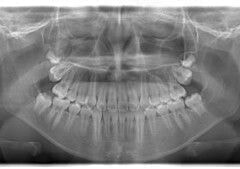

小児期ケース:反対咬合+上顎両側3番埋伏歯

(受け口+右上3番目の永久歯が埋まってしまい、はえてこない)

治療法:上顎急速拡大装置+クリアスナップ+フェイスマスク+上顎右側3番は開窓萌出誘導

(難症例のため、小児期の矯正を2段階にわけました)